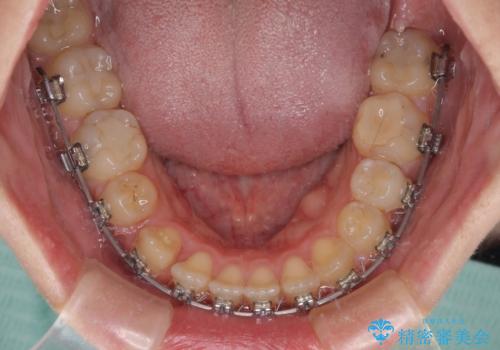

八重歯を抜歯矯正でスッキリと メタルブラケットでの矯正治療

- 矯正装置

- メタルブラケット

- 八重歯と上下前歯のでこぼこを気にして来院された患者様です。

上下前歯部叢生のスペース獲得のため、上下顎左右小臼歯各1歯(計4本)と全ての親知らずを抜歯して、矯正治療を行うこととしました。